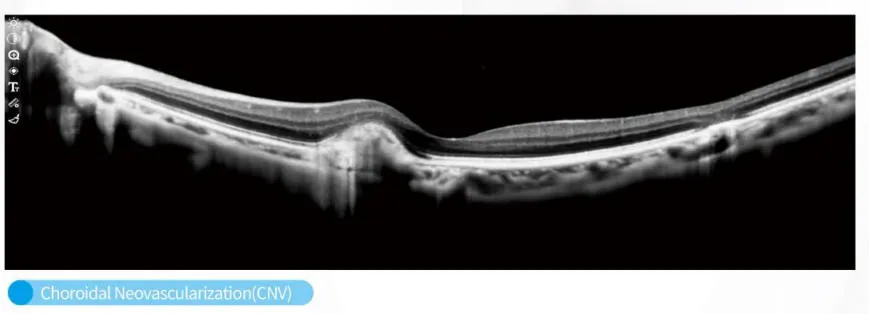

OCT Imaging Analysis

OCT Structural Scan

The C800 incorporates automatic eye-tracking, SLO scanning, and multi-mode tomographic imaging, ensuring stable visualization even for patients with difficulty maintaining fixation. Advanced choroidal thickness measurement and macular mapping support precise monitoring for myopia control, diabetic retinopathy, glaucoma, and age-related macular degeneration.

It is ideal for monitoring and detecting myopia, diabetic retinopathy, glaucoma, and age-related macular degeneration through advanced choroidal and macular mapping.